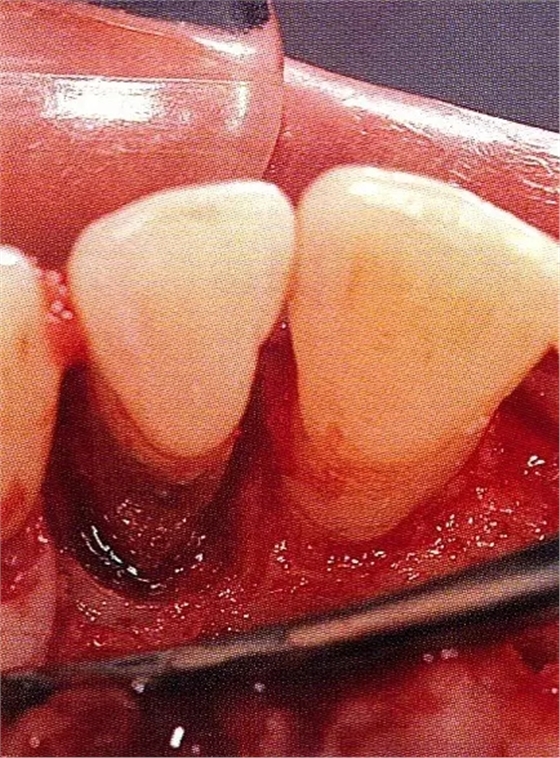

案例3針對(duì)3壁性垂直性骨缺損使用非吸收性膜進(jìn)行再生治療,再翻瓣時(shí)進(jìn)行骨形態(tài)修整的病例。

▲圖7-1左下6近中可觀察到3壁性垂直性骨缺損。此病例考慮到齦瓣供血關(guān)系,在前磨牙部位進(jìn)行了減張切開,沒有進(jìn)行縱切開。并利用刮治器、牙周外科用車針進(jìn)行了徹底的骨缺損部位搔刮。